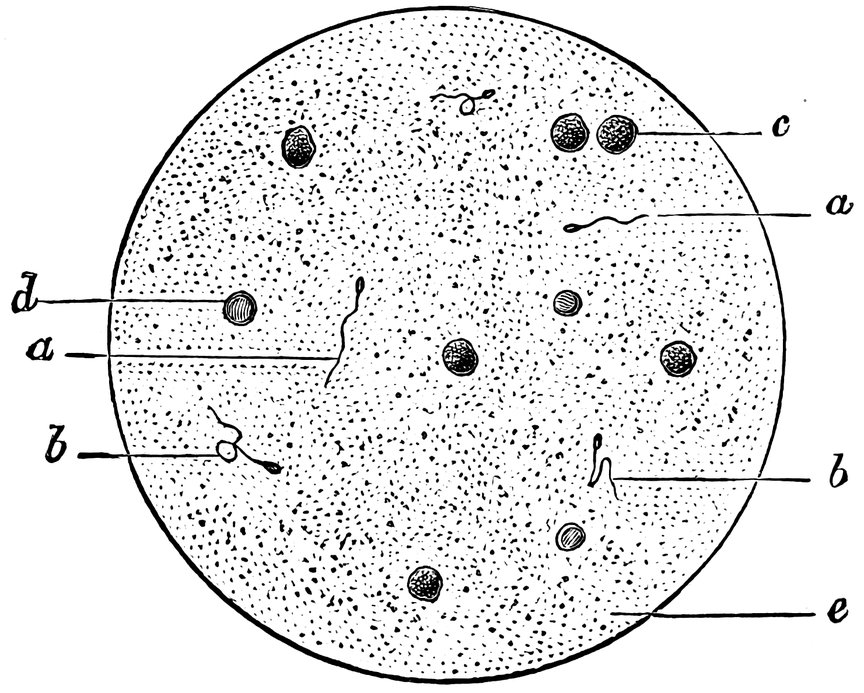

| 61. | a. b. c. Prostatic calculi from normal semen, d. Spermatozoa. e. Large and small cells, some containing granules, as morphological elements of semen. f. Spermatozoon distorted by imbibition of water. g. Crystals (after Bizzozero) | 311 |

| 62. | Normal Semen | 311 |

| 63. | Semen consisting chiefly of sperm-crystals, cylindrical epithelium, and small granules exhibiting molecular movement—but containing no spermatozoa | 315 |

| 64. | Oligozoöspermia. a. Living Spermatozoa, b. Dead Spermatozoa, c. Pus Corpuscles, d. Erythrocyte, e. Seminal granules | 317 |